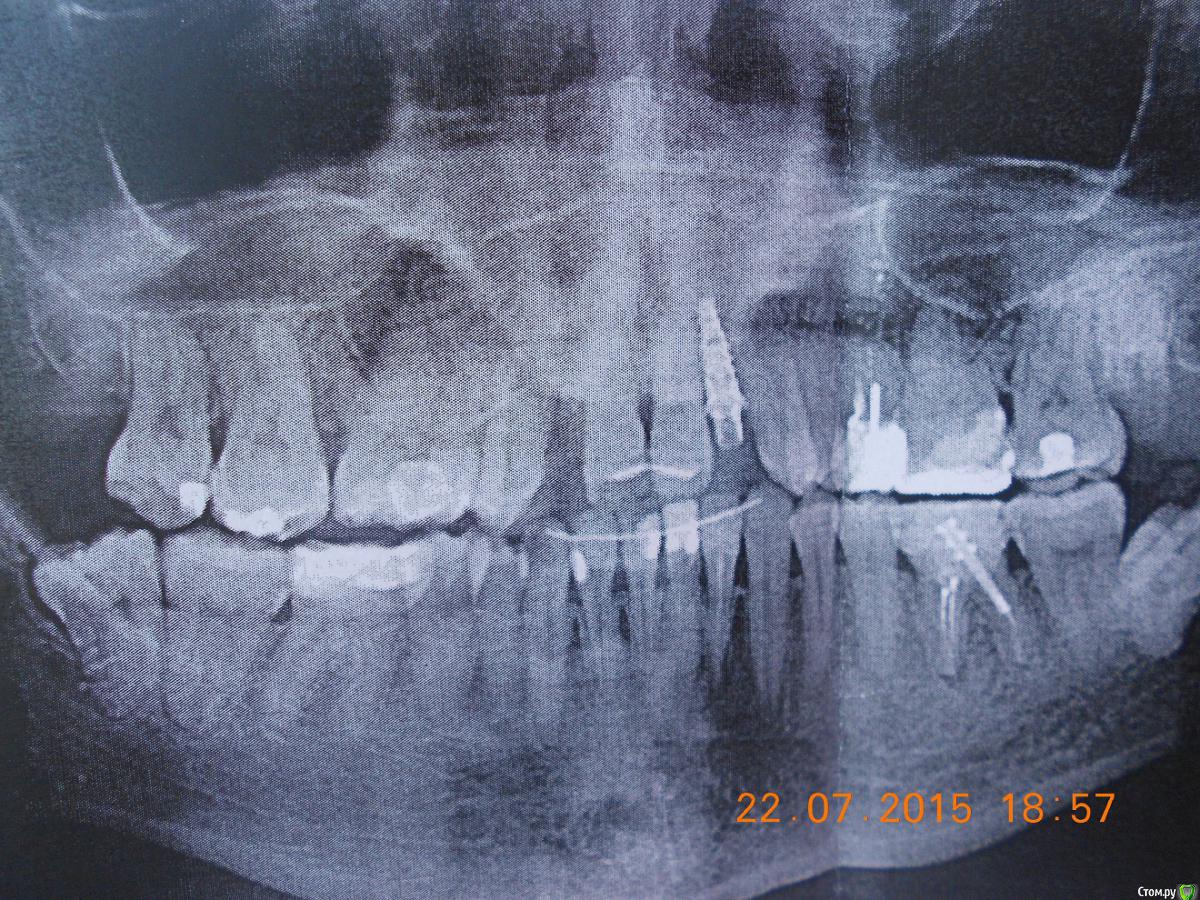

holodova.viktori Опубликовано 22 июля, 2015 Поделиться Опубликовано 22 июля, 2015 Добрый день, прошу помочь принять решение,что делать с имплатном.Поставили на ВЧ два импланта в октябре. Операция вроде бы прошла успешно, ничего не беспокоило. Через 4 мес. установили формирователь десны, проде бы тож все нормально было (снимки прилагаю).Еще через 2 недели отправили к ортопеду. И вот тут когда стал он выкручивать формирователь- стало больно очень-очень внутри кости , итог-имплант выкрутили. На второй имплант установили временную коронку и я с ней отходила ок. 3мес.,вокруг десны возникло локальное воспаление-отправили к пародонтологу,он к хирургу опять,хирург ничего критичного в импланте не увидел.Воспаление прошло-метрогилом мазала,календулой полоскала. И вот когда ортопед стал выкручивать временную коронку-стало опять больно,боль внутри кости опять.Послали на снимки. Хирург посмотрел снимки, потрогал зуб(временный кот), грит наблюдается убыль кости и подвижность имплатна 1 ст. И сейчас предлагает либо не трогать ничего и ходить с временной коронкой столько-сколько прохожу (грит от 2 мес. до неск.лет, те вопрос выпадения импланта-эт вопрос времени просто), либо удалять имплант.Консультировалась с несколькими др. хирургами они грят-необх.откручивать временную коронку и смотреть что с имплантом-выдерживает ли он нагрузку или подвижен, ели подвижен-удалять однозначно, ждать 6-9 мес. пока восстановится объем костной ткани и потом решать что делать дальше.И пока ходить со съемными протезами.И все они грят,что изначально места было недостаточно,для имплантов и есть ошибки хирурга на стадии планирования операции и выбора р-ра имплантов.Очень прошу прокомментировать ситуацию. Ссылка на комментарий

Aquarius Опубликовано 22 июля, 2015 Поделиться Опубликовано 22 июля, 2015 Ну судя по рентгену - ситуация выглядит не очень хорошей. А можете сфотографировать во рту?? Ссылка на комментарий

krokomot Опубликовано 22 июля, 2015 Поделиться Опубликовано 22 июля, 2015 Я так понимаю боковые резцы у вас всю жизнь отсутствовали.По мне имплант слишком близко расположен к корням соседних зубов. Прогноз у него весьма сомнительный. 1 Ссылка на комментарий

SashaDoc Опубликовано 22 июля, 2015 Поделиться Опубликовано 22 июля, 2015 Имплант удаляйте, пока хоть какой-то объем тканей вокруг сохранен 3 Ссылка на комментарий